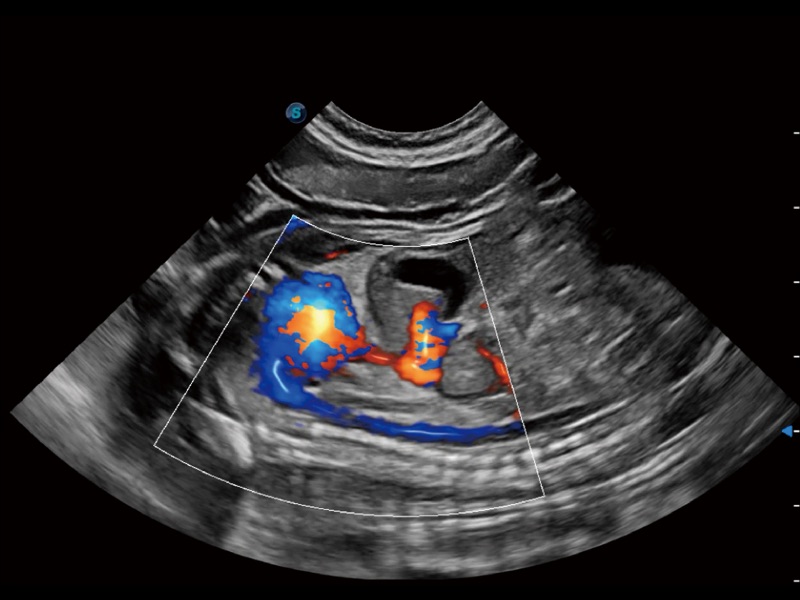

通過(guò)創(chuàng)新的 Matrix E自適應(yīng)濾波器和超長(zhǎng)時(shí)間域算法,極大提升超低速微細(xì)血流的檢出能力,同時(shí)更精準(zhǔn)地濾除軟組織和噪聲信號(hào),為獸用醫(yī)生提供以往無(wú)法通過(guò)常規(guī)血流獲得的疾病診斷信息。

通過(guò)色彩血流和實(shí)時(shí)寬景相結(jié)合,可觀察到完整的靜脈或動(dòng)脈的血流,方便醫(yī)生檢查。實(shí)時(shí)掃查過(guò)程中,如有任何操作失誤也可以很容易地進(jìn)行回掃擦除,而不會(huì)中斷掃查。